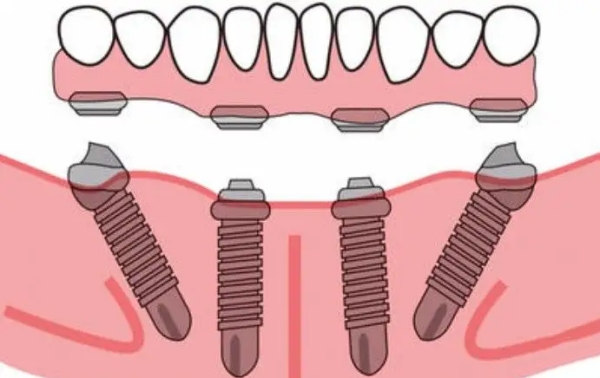

如果你缺了半口或全口牙,數(shù)字化種植的優(yōu)勢(shì)較大。傳統(tǒng)種牙需要種很多顆,手術(shù)時(shí)間長、創(chuàng)傷大。而數(shù)字化種植可以用更少的種植體支撐整排假牙,比如All-on-4技術(shù),只需要種4顆種植體就能支撐半口假牙。